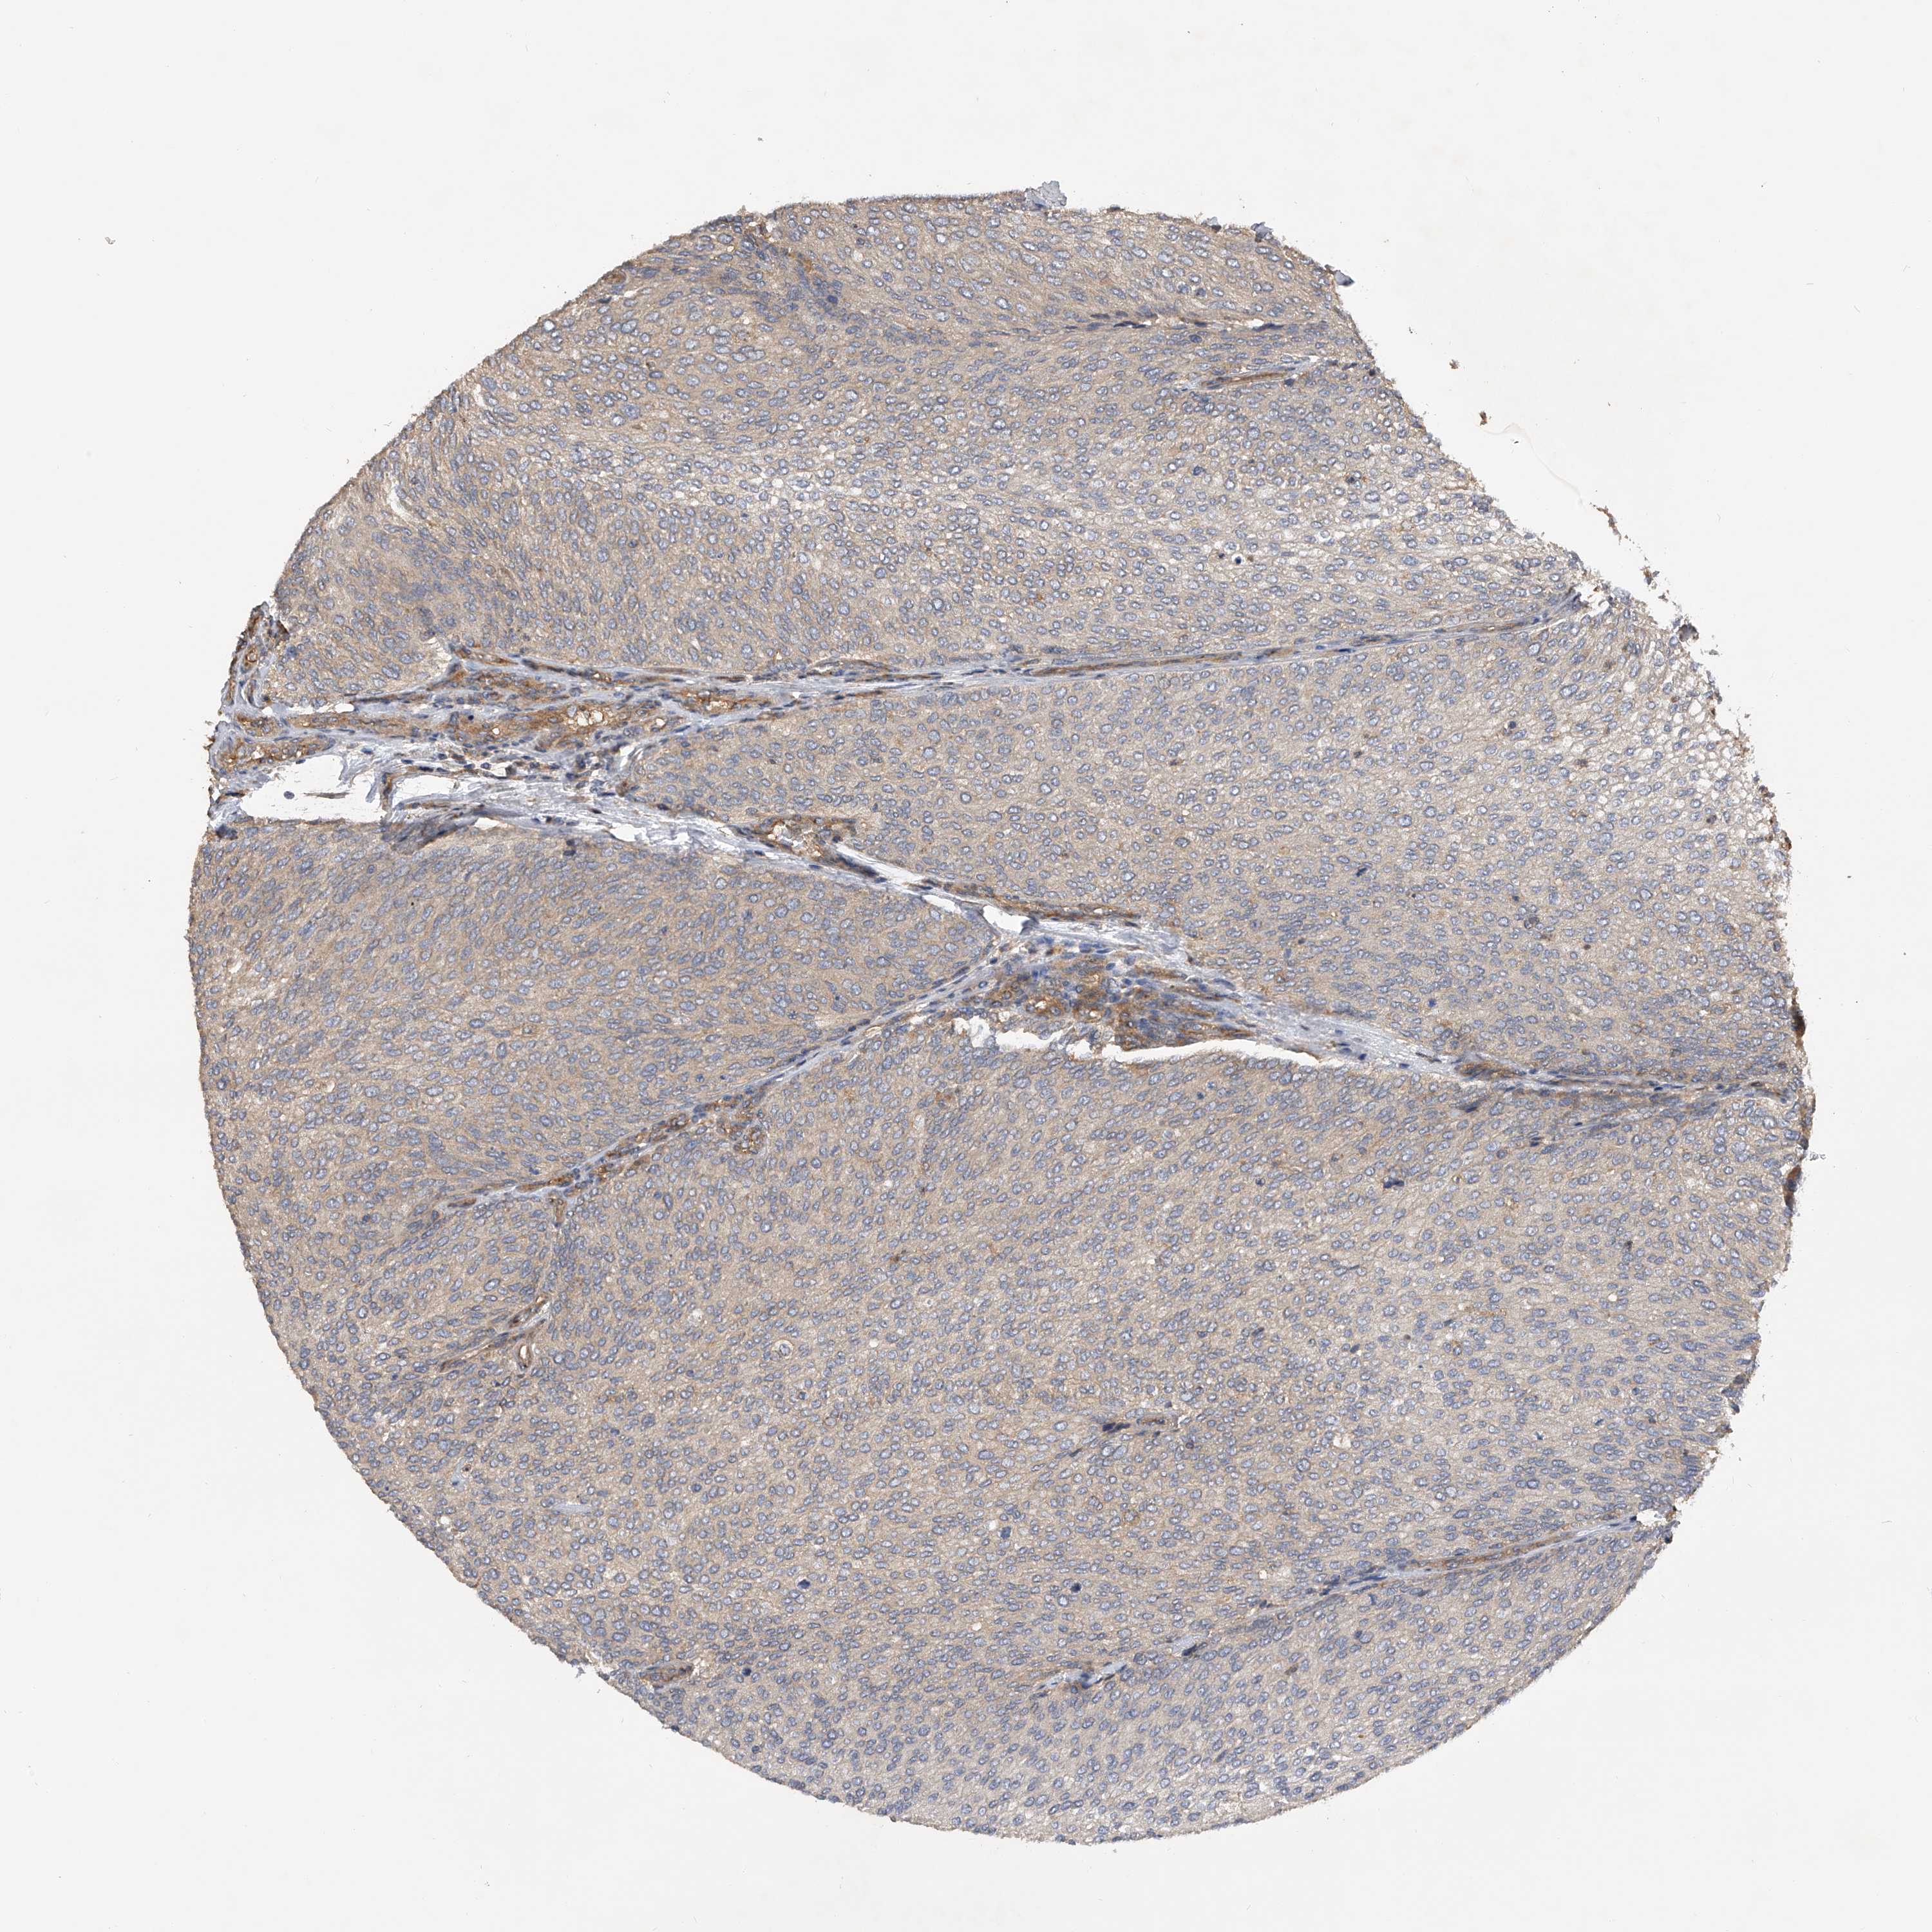

UROTHELIAL CANCER - Protein expressioni

A mouse-over function shows sample information and annotation data. Click on an image to view it in a full screen mode. Samples can be filtered based on level of antibody staining by selecting one or several of the following categories: high, medium, low and not detected. The assay and annotation is described here.

Note that samples used for immunohistochemistry by the Human Protein Atlas do not correspond to samples in the TCGA dataset.

Antibody stainingi

Antibody staining in the annotated cell types in the current human tissue is reported as not detected, low, medium, or high, based on conventional immunohistochemistry profiling in selected tissues. This score is based on the combination of the staining intensity and fraction of stained cells.

Each image is clickable and will lead to virtual microscopy that enables deeper exploration of all samples and also displays staining intensity scores, fraction scores and subcellular localization as well as patient and tissue information for each sample.

Antibody HPA029412

Antibody CAB034366

Urothelial carcinoma, Low grade

Urothelial carcinoma, High grade